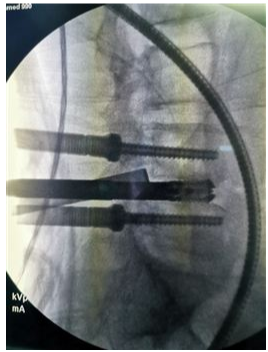

奧蘇本UBE技術(shù)概UBE技術(shù)即單側(cè)雙通道內(nèi)鏡技術(shù)(Unilateral Biportal Endoscopy Technique),適用于頸椎、胸椎、腰椎的退行性病變。與椎間孔鏡的單通道不同,該技術(shù)通常建立兩個(gè)通道,一個(gè)為觀察通道,一個(gè)為器械操作通道。觀察通道一般會(huì)用到0°或30°UBE內(nèi)鏡,操作通道使用UBE專器械,如UBE刮匙、磨鉆(UBE內(nèi)鏡磨頭)、UBE內(nèi)鏡刨刀、UBE內(nèi)鏡消融電極、UBE椎板咬骨鉗、UBE髓核鉗、UBE神經(jīng)拉鉤等。UBE技術(shù)的專用器械包,通過(guò)UBE技術(shù)還可以完成鏡下融合手術(shù)。

該技術(shù)開展脊柱手術(shù)時(shí),克服了中心管狹窄、側(cè)管狹窄和椎間孔狹窄的局限。手術(shù)入路角度范圍廣,在不損傷脊柱結(jié)構(gòu)完整性的前提下,有效地對(duì)椎管進(jìn)行了周向和局部減壓,保留了肌肉韌帶附著通過(guò)肌間間隙,保護(hù)背支內(nèi)側(cè)支,從而防止?fàn)繌垞p傷。這種內(nèi)窺鏡入路允許從對(duì)側(cè)后入路和孔外入路(椎旁孔外入路)進(jìn)入孔,為治療所有類型的狹窄提供了靈活性,因此,UBE技術(shù)作為一種微創(chuàng)的融合方法,具有極強(qiáng)的實(shí)用性。

1、UBE內(nèi)鏡直徑小,操作空間大,移動(dòng)范圍廣;

2、應(yīng)用傳統(tǒng)脊柱外科器械即可,不受特殊器械限制,普通尺寸器械處理增生退變組織效率更高;

3、比孔鏡更容易處理狹窄病例;

4、水介質(zhì)中操作,視野更加清晰,特殊器械可保持順暢出水;

5、熟悉的后方入路,學(xué)習(xí)曲線低;

6、適應(yīng)癥廣泛,能輕松完成鏡下融合、頸椎、胸椎、腰椎等復(fù)雜病例。